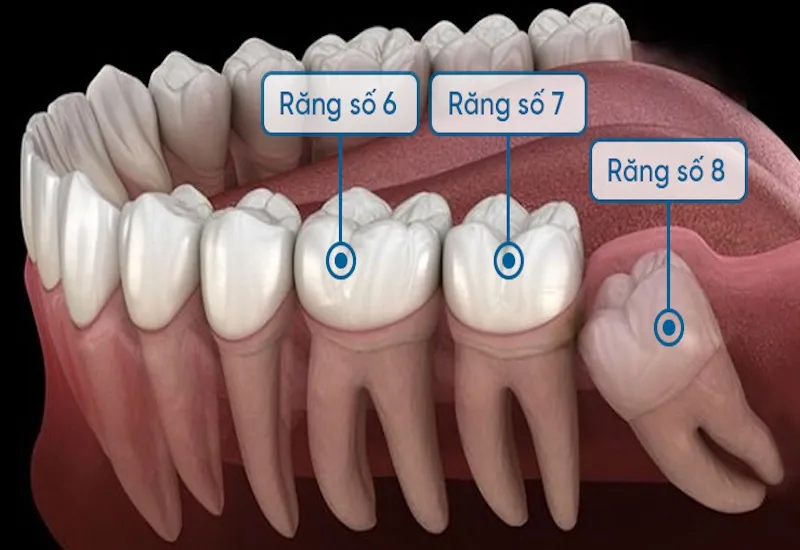

Chân răng số 8 là phần quan trọng cấu thành chiếc răng khôn – răng mọc cuối cùng trên cung hàm của mỗi người. Việc hiểu rõ

Chân răng số 7 là một bộ phận quan trọng trong hệ thống răng hàm mặt, đảm nhận vai trò thiết yếu trong việc ăn nhai và

Chân răng số 6 là một phần quan trọng của răng số 6, một trong những chiếc răng vĩnh viễn lớn, đóng vai trò chủ chốt trong